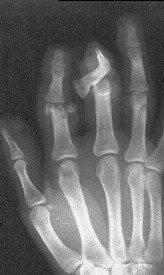

Уважаемые коллеги, в травмотделение БСМП Ангарска поступил пациент с отрывом 3 пальца на уровне проксимального межфалангового сустава (дистальная

часть пальца висит на кожном лоскуте с латеральной стороны пальца шириной 1 см, повреждены сухожилия сгибателей и разгибателей), многооскольчатым переломом головки основной фаланги 2 пальца, рваной раной в проекции сустава, превышающей половину диаметра пальца (сухожилия целы)(снимок 1, снимок 2). Выполнена ПХО ран, МОС спицами трансартикулярно (снимок 3, снимок 4). При обсуждении тактики лечения возникли разногласия между врачом, выполнявшим ПХО, и заведующим. Зав. отделением считает, что выбранная тактика неверна, и необходимо было после проведения ПХО сделать вытяжение типа Черкес-Заде за пальцы. Просим высказать присутствующих свое мнение о выполненной операции и о дальнейшей тактике лечение больного. Заранее спасибо.